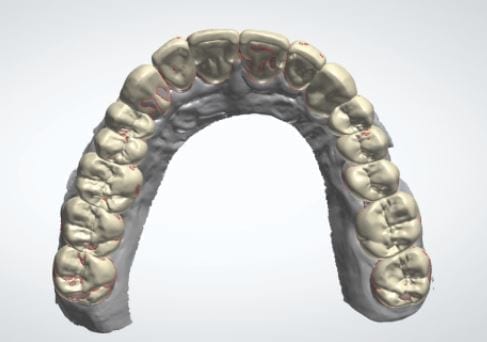

The digital models were then imported into a third party software where a library of tooth morphologies are available for the clinician to choose from.

Once the appropriate library is chosen, the digital wax ups are performed. In the subsequent photos you can see the transparent overlay of the wax-ups to the original position of the existing dentition

The case was designed by CADENT BESSA, and the models were printed by Burbank Dental Lab with Carbon Printers. There restorations were milled and cut back and layered by Burbank Dental Lab